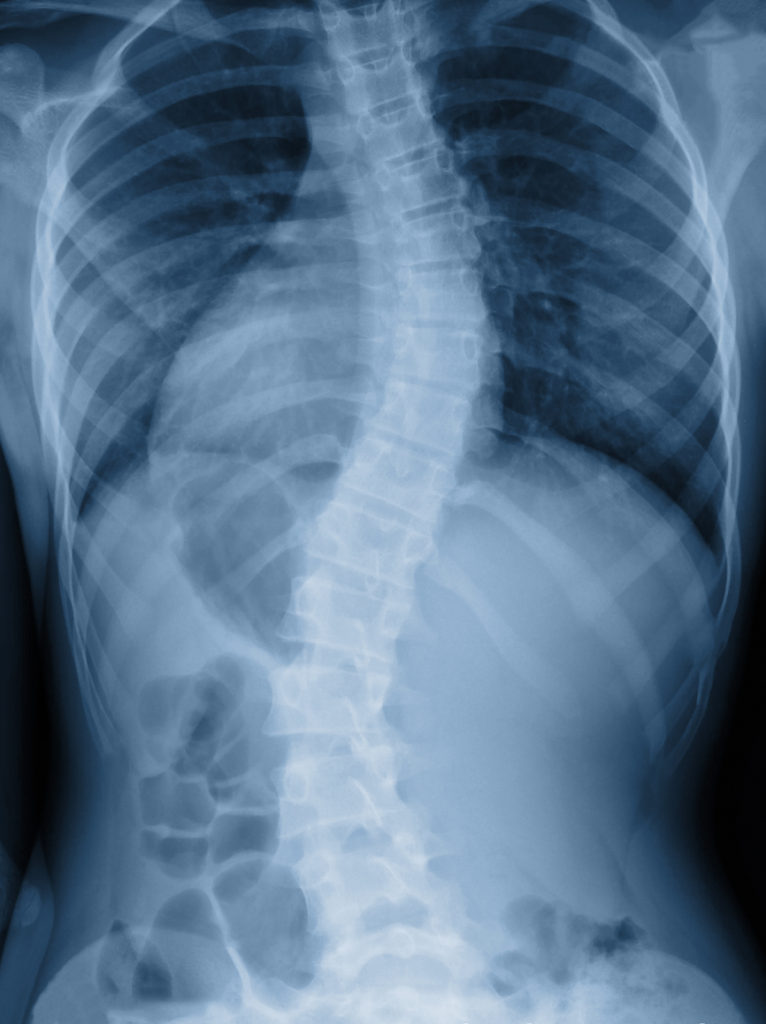

Scoliosis Lower back Manchester Physio Leading Physiotherapy Does Massage Therapy Help Scoliosis while massage therapy for scoliosis cannot fix the underlying cause, medical research has found that it can. Some key benefits include increased body awareness. Whether from a professional or a massage chair, it enhances the daily life of scoliosis patients. massage is a method that’s often used to combat backache, but can massages help scoliosis patients specifically? . Does Massage Therapy Help Scoliosis.